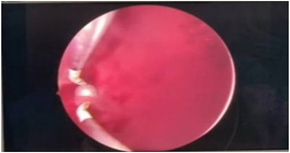

Cystoscopy was done to detect mucosa lesions in bladder; the whole mucosa was congested and red. There were multiple hemorrhagic areas in whole bladder mucosa; it was bled on touch. There was no focal ulcer or tumor. Therefore, generalized congested mucosa, hemorrhagic areas were probably due to DIC or CMV cystitis or candida cystitis or bacteria cystitis. The color of urine coming from Vescio-ureteric orifice of graft kidney was clear. Hemostasis was done with Ball electrode; bladder wash out was done with Tomey’s glass syringe. Figure 9-15 reveal cystoscopy findings. Abdominal tomogram was done; it revealed a swollen allograft kidney with air in the renal pelvis and renal vessels and subcapsular area suggestive of emphysematous allograft pyelonephritis. And, air along bladder wall was seen indicating emphysematous cystitis. They are illustrated in (Figure 16-19).